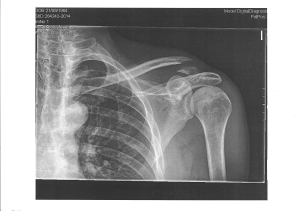

Y como se puede apreciar, me rompí la clavícula. Ahora llevo dos clavos que la sujetan y que presumiblemente favorecerán que suelde adecuadamente. Maravillas de la técnica y de la sanidad pública.